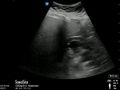

Abnormal

- Hydronephrosis

- Mild: Distention of collecting system

- Moderate: Dilation of collecting system, rounding of calyces

- Severe: Dilated renal calyces and cortical thinning[2]

- “Bear claw” appearance

- Represents severe obstructive uropathy